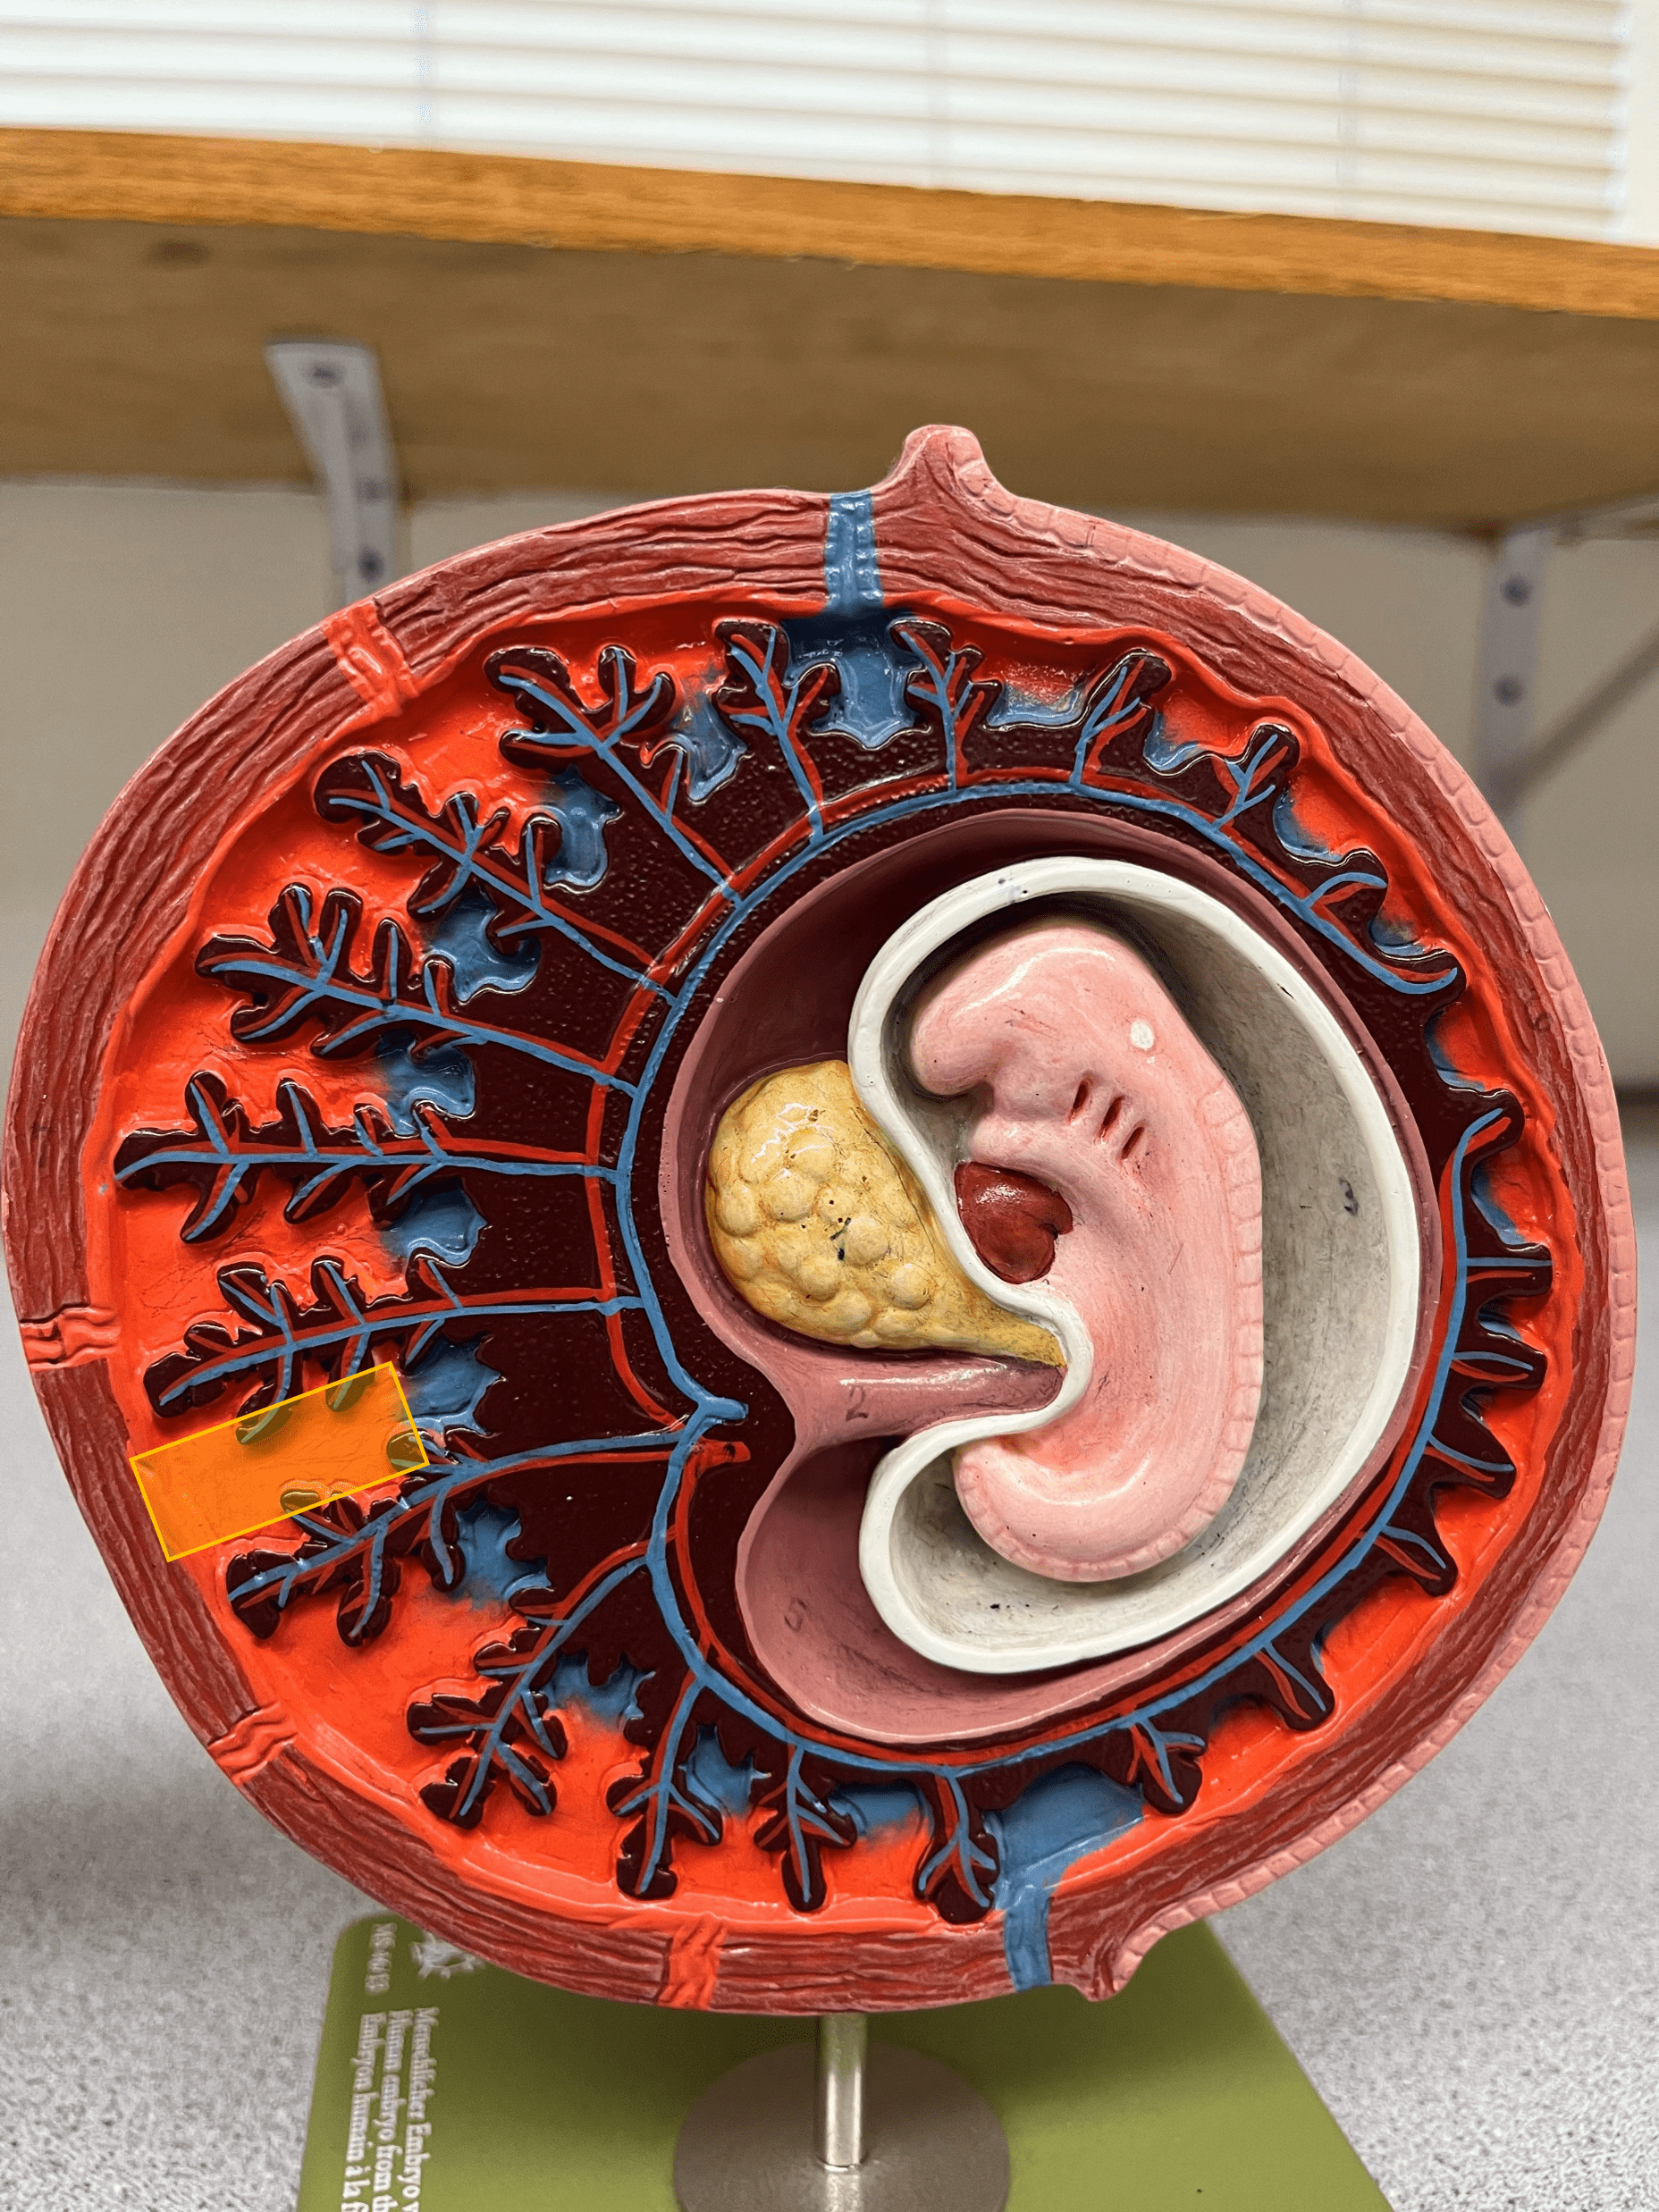

• Model of the 30-day embryo.

• Extensions of the chorion that bring fetal and maternal blood into close proximity to allow diffusion of nutrients and wastes.

• Contains vessels.

• Model of the 30-day embryo.

• The maternal portion of the placenta that exchanges nutrients and wastes with chorionic villi vessels.

• Also known as a placental sinus.